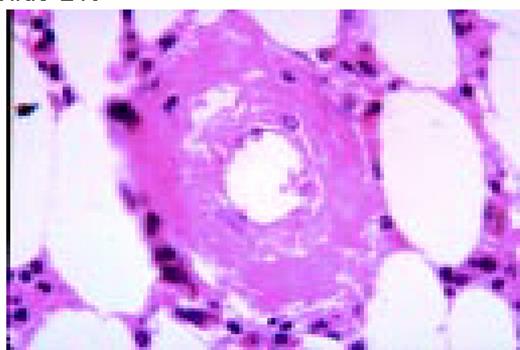

Slide L48

Amyloid, bone marrow biopsy, H&E stain. A small blood vessel is heavily infiltrated with the pink-staining, waxy amyloid material.FIG48